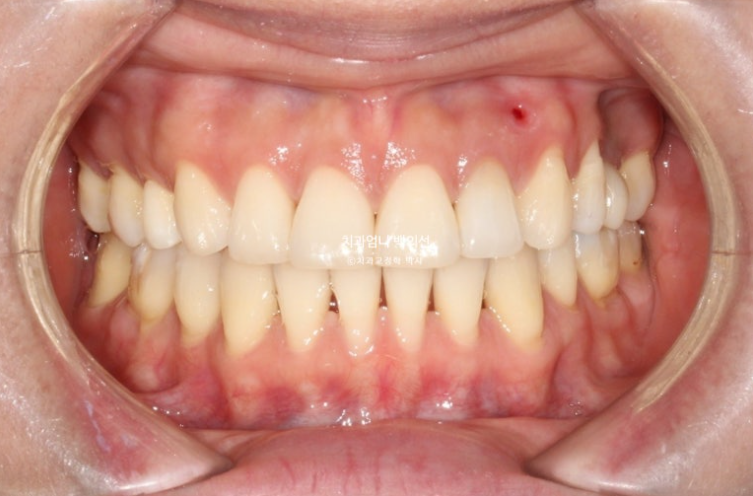

교합 안정화 및 마무리과정을 거쳐 25년 6월 드디어 재교정 치료를 마무리 했습니다.

25.06

총 치료기간은 1년 10개월입니다.

이제 앞니 중심선은 코와 인중과 정확히 맞습니다.

2급이었던 양측 어금니 교합관계는 비로소 1급이 되었습니다.